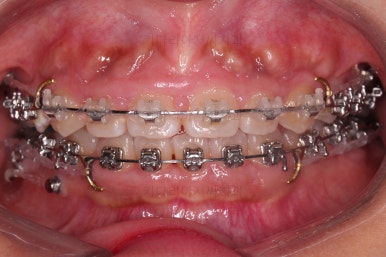

오늘 소개해 드릴 환자분은 아래 앞니가 하나 없는 결손치아, 그로 인해서 윗니 앞니가 뒤로 굽어 들어오는 "옥니", 그로 인해 위아래 앞니가 많이 겹치는 과개교합 및 잇몸웃음(거미스마일)이 나타나는 복합적인 문제가 있는 분이셨습니다.

사용한 장치 : 자가결찰 메탈 + 세라믹 복합(엠파워 메탈, Empower metal + 세라믹) + 미니스크류

과개교합이 어느 정도 개선이 되어서 아래 앞니가 서서히 보이기 시작하네요.

이번 부산옥니교정 환자분이 선택하신 장치는 엠파워인데 윗니는 덜 보이는 세라믹, 아랫니는 메탈입니다.

같은 엠파워 장치이기 때문에 이렇게 섞어 써도 문제가 전혀 없는데요.

흔히 아시는 클리피씨로 하자면 윗니는 클리피씨 + 아랫니는 클리피엠(M)인 셈이죠.

윗니는 세람기으로 해서 심미성을 강조하고 아랫니는 좀 더 부피가 작고 강하여 과개교합 교정에 유리하며 저렴하기도 한 메탈로 했습니다.

장치 부착 직후의 모습입니다.